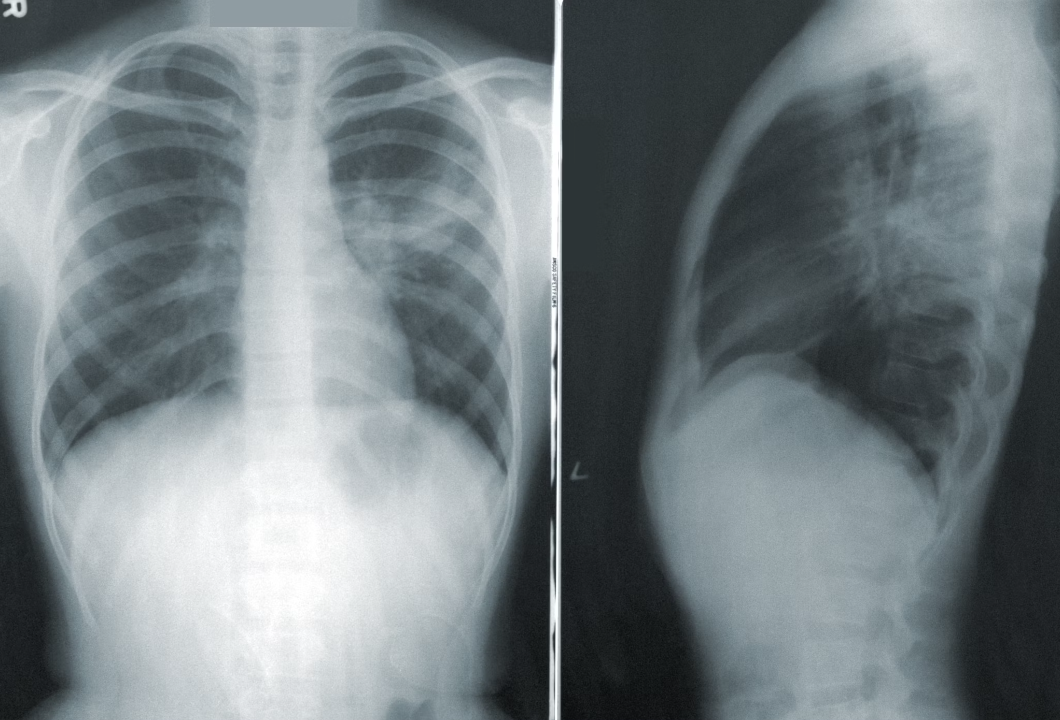

Фтизиатр призвал больных туберкулезом жителей Cамарской области соблюдать режим изоляции и лечения

24 марта - Всемирный день борьбы с туберкулезом. 142 года назад был открыт возбудитель опасного заболевания.